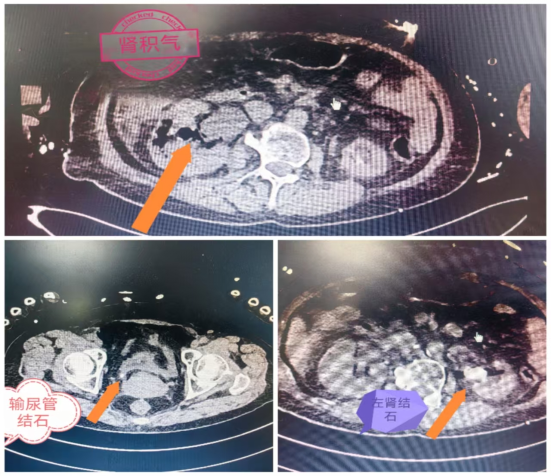

陈女士有14年糖尿病史,长期血糖管理混乱。两天前出现腰腹胀痛、恶心发热(体温达39℃),自行用药后症状加重昏迷。送医后,血压低至76/51mmHg,血糖19.7mmol/L,CT显示肾及输尿管积气、结石伴积水,确诊为气肿性肾盂肾炎合并感染性休克。经泌尿外科紧急抢救、排脓抗感染及碎石手术,才转危为安。

腹部增强CT能精准诊断,确诊后及时治疗可保肾救命:先排脓减压,再用精准抗生素杀菌,同时严控血糖。